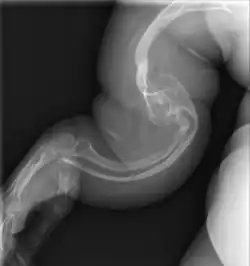

Type II

Collagen is fatally defective at its C-terminus.[5]: 1512 Most cases result in death shortly after birth, or within the first year of life, due to respiratory failure. Another common cause of death is intracranial bleeds from skull fractures present at, or sustained during or shortly after, birth.[5]: 1511 In many cases, the newborn already has multiple broken bones at the time of birth. Type II infants also exhibit severe respiratory problems and have severely deformed bones. Sixty percent of infants die less than 24 hours after being born, and survival after the first year is extremely unlikely and normally requires mechanical ventilation.[57] In the rare cases of infants who survive their first year of life, severe developmental and motor delays are seen; neither of two infants studied in 2019, both aged around two years, had achieved head control, and both required a ventilator to breathe.[58]

Type II is also known as the "lethal perinatal" form of OI,[59] and is not compatible with survival into adulthood.[57] Due to similarly severely deformed bones, sometimes infants with severe type III are wrongly initially classified as type II; once long-term survival is shown, they are considered as having type III instead.[5]: 1511 [60]

Diagnosis is typically based on medical imaging, including plain X-rays, and symptoms. In severe OI, signs on medical imaging include abnormalities in all extremities and the spine.[97] As X-rays are often insensitive to the comparatively smaller bone density loss associated with type I OI, DEXA scans may be needed.[5]: 1514

An OI diagnosis can be confirmed through DNA or collagen protein analysis, but in many cases, the occurrence of bone fractures with little trauma and the presence of other clinical features such as blue sclerae are sufficient for a diagnosis. A skin biopsy can be performed to determine the structure and quantity of type I collagen. While DNA testing can confirm the diagnosis, it cannot absolutely exclude it because not all mutations causing OI are yet known and/or tested for.[83]: 491–492 OI type II is often diagnosed by ultrasound during pregnancy, where already multiple fractures and other characteristic features may be visible. Relative to control, OI cortical bone shows increased porosity, canal diameter, and connectivity in micro-computed tomography.[98] OI can also be detected before birth by using an in vitro genetic testing technique such as amniocentresis.[99]